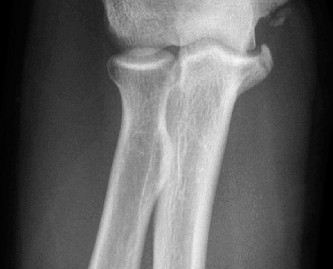

On examination, he has tenderness to palpation over his olecranon and pain with terminal elbow extension. He has no evidence of varus or valgus instability. No pain with resisted wrist flexion. His images are shown (Figs. 2–108 to 2–110).

Figure 2–108

Figure 2–109